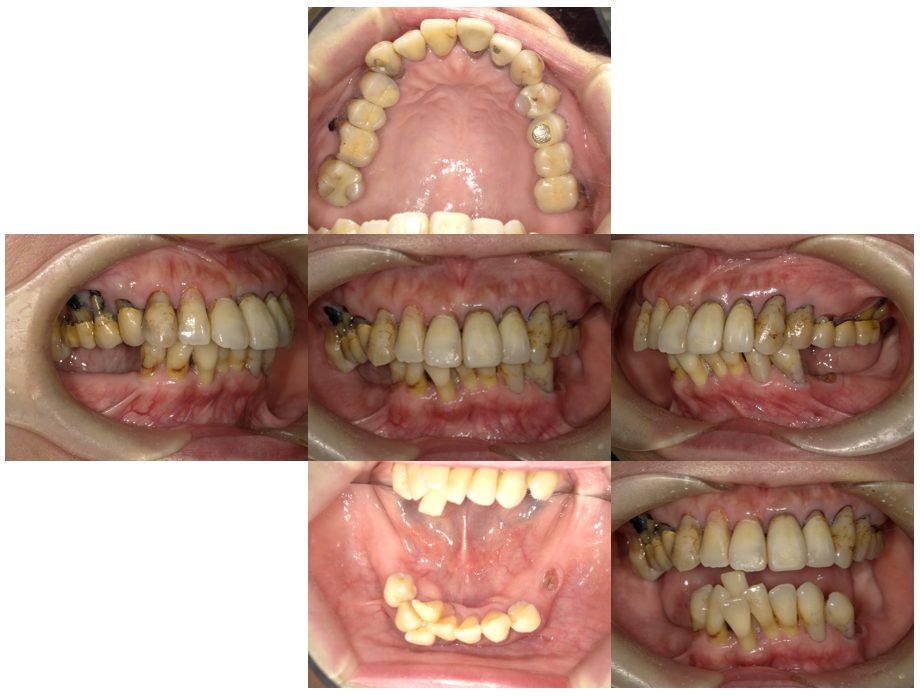

インプラント治療・セラミック治療・金属床コーヌス義歯(部分入れ歯)の症例紹介(三隅歯科クリニック)

三隅 賢祐(三隅歯科クリニック)

症例詳細

| 主訴 | 50代女性 他院でいれた入れ歯の具合が良くない。歯を白くしたい。歯並びも気になる。しっかり噛めるようになりたい |

| 治療内容 | インプラント治療、セラミック治療、金属床コーヌス義歯(部分入れ歯)を行いました。 |

| 治療費 | 2,400,000円(税込み) |

| 治療期間 | 8か月 |

| 治療回数 | 30回 |

| 想定されたリスク | 重度の歯周病で臼歯部の歯槽骨がかなり吸収していたため、インプラントが脱落するリスクがありました。 |